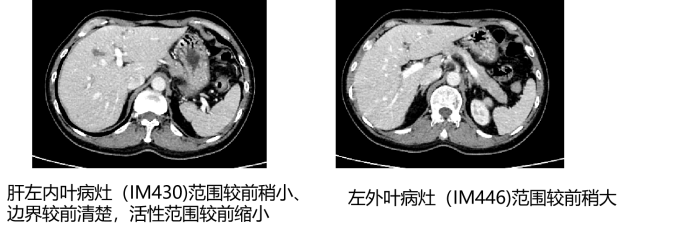

• MRI增强(2025年5月21日):肝脏多发转移灶,其中肝左内叶病灶未见确切活性,部分病灶仍有活性;部分胸腰椎内异常信号,考虑转移。

image.png